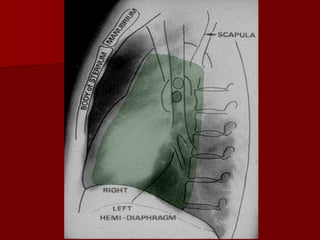

Retrosternal Clear Space

Retrocardiac Clear Space

Left Hemidiaphragm

Stomach gas bubble

Splenic flexure of the

large intestines

Right Hemidiaphragm

Liver

some of the visual abdominal structures

Lateral view

The only view that provides information of

localization of different lobes and segments

 Observation on lateral view include- clear

spaces, vertebral translucency , and outline of

diaphragms.